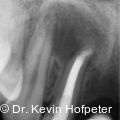

Apikale Läsionen mit ausgeprägter Ausdehnung stellen in der endodontischen Behandlung eine besondere Herausforderung dar. Radiologisch sichtbare Defekte von mehr als einem Zentimeter werden klinisch häufig als Zysten interpretiert. Fotos: © Dr. Kevin Hofpeter